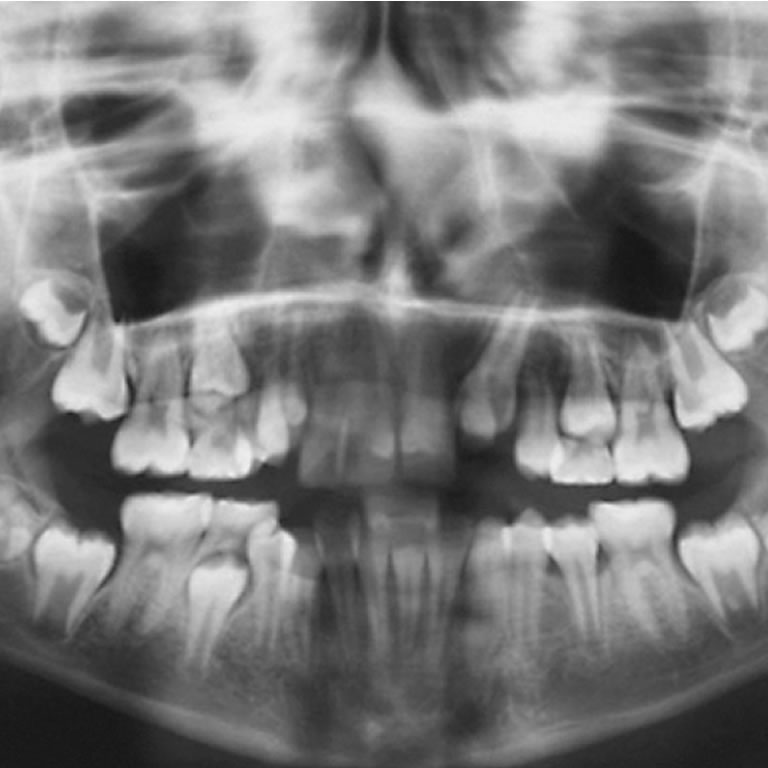

Regeneracion de Tejidos Dentario

Dra. Elena Pruskin

Los tratamientos endodónticos no quirúrgicos en dientes inmaduros infectados suelen ser exitosos, pero no regeneran los tejidos ni permiten el desarrollo normal del ápice. Así, la apexogénesis no se logra mediante estas terapias convencionales.